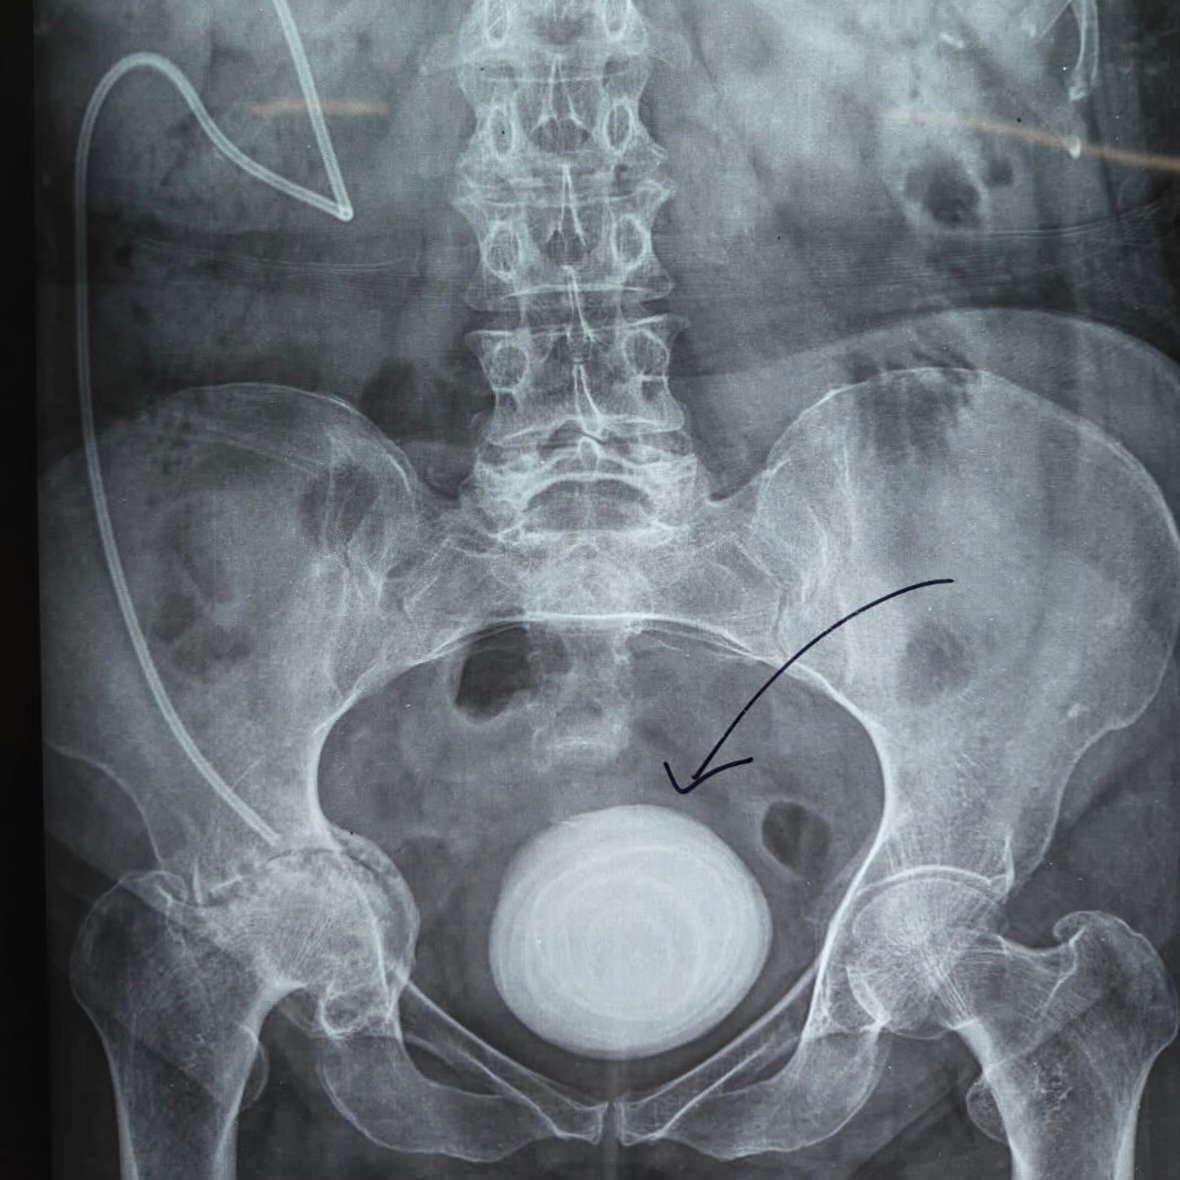

(शहजाद अली हरिद्वार)हरिद्वार। बहादराबाद स्थित जया मैक्सवेल हॉस्पिटल में डॉक्टरों की टीम ने एक बेहद जटिल और हाई-रिस्क सर्जरी को सफलतापूर्वक अंजाम देकर मरीज को नई जिंदगी दी। अस्पताल के यूरोलॉजी विभाग के वरिष्ठ सर्जन डॉ. विपिन तिवानी के नेतृत्व में यह ऑपरेशन किया गया, जिसमें मरीज के मूत्राशय से 14 सेंटीमीटर की विशाल पथरी को सुरक्षित तरीके से बाहर निकाला गया।

जानकारी के अनुसार, मरीज लंबे समय से पेशाब की कमजोरी, तेज जलन, दर्द और रुक-रुक कर खून आने जैसी गंभीर समस्याओं से जूझ रहा था। जांच के दौरान उसके ब्लैडर में बड़ी पथरी (वेसिकल कैल्कुलस) का पता चला।स्थिति तब और चुनौतीपूर्ण हो गई जब मरीज का पुराना मेडिकल इतिहास सामने आया। उसे पहले ट्यूबरकुलर मेनिनजाइटिस हो चुका था, जिसके कारण पैरालिसिस की स्थिति बनी और वीपी शंट सर्जरी भी की जा चुकी थी।

इन जटिल परिस्थितियों के चलते पहले तीन अस्पतालों ने ऑपरेशन करने से साफ इनकार कर दिया था। हालांकि, जया मैक्सवेल हॉस्पिटल की टीम ने इस चुनौती को स्वीकार करते हुए ऑपरेशन का निर्णय लिया। करीब दो घंटे तक चली सर्जरी में डॉक्टरों ने अत्यंत सावधानी और सटीक रणनीति के साथ पथरी को सफलतापूर्वक निकाल दिया।

डॉ. विपिन तिवानी ने बताया कि मरीज की न्यूरोलॉजिकल स्थिति और वीपी शंट के कारण एनेस्थीसिया देना भी जोखिम भरा था, लेकिन बेहतर टीमवर्क और प्लानिंग के चलते ऑपरेशन सफल रहा।फिलहाल मरीज की हालत स्थिर है और उसमें तेजी से सुधार हो रहा है। पेशाब संबंधी दिक्कतों में भी राहत मिली है। अस्पताल प्रबंधन का कहना है

कि उनका उद्देश्य गंभीर से गंभीर मरीजों को भी सुरक्षित और बेहतर इलाज उपलब्ध कराना है। यह सफलता उन मरीजों के लिए उम्मीद की किरण बनी है, जिन्हें हाई-रिस्क बताकर इलाज से मना कर दिया जाता है।